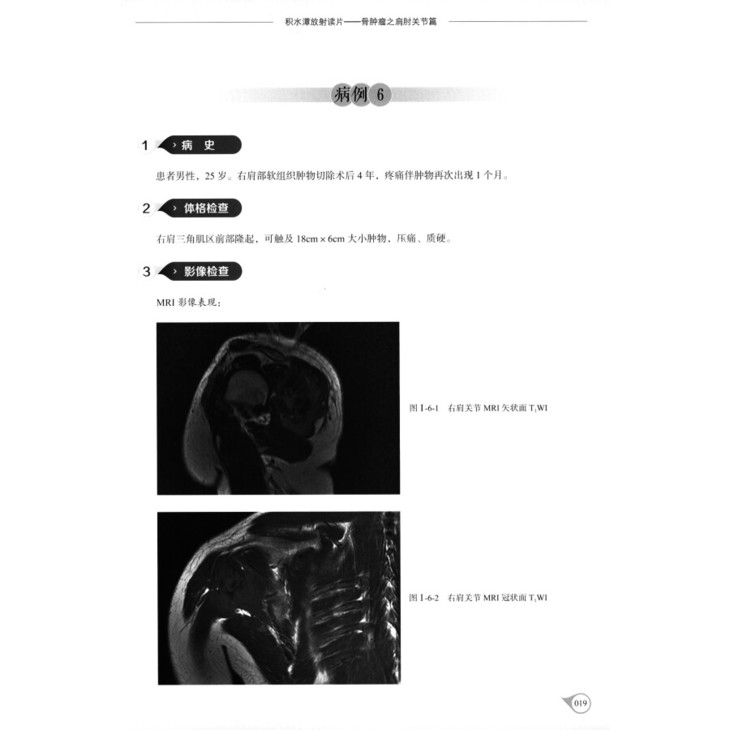

病例6